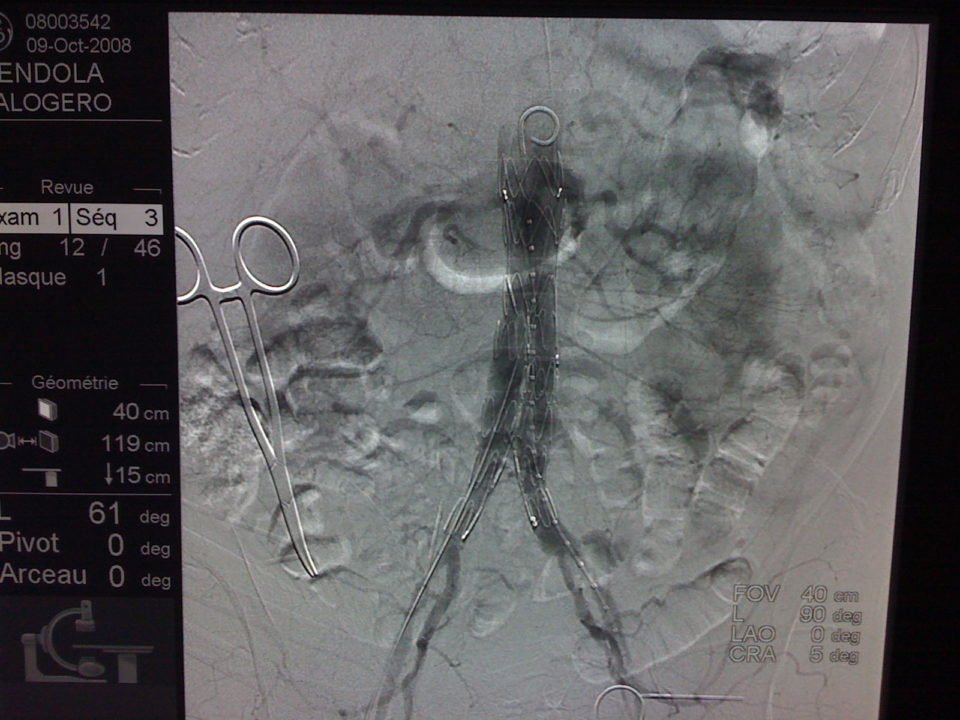

L’angioscanner aorto-iliaque est plus invasif mais plus reproductible que l’échographie et moins opérateur dépendant. C’est l’examen de choix avant un traitement par endoprothèse ou par chirurgie classique. Il permet les mesures exactes (« sizing ») de l’anatomie de l’anévrysme, de l’aorte et des artères iliaques avant mise en place d’une endoprothèse. Il permet la recherche d’autres anévrysmes au niveau fémoro-poplités et d’étudier l’ensemble de l’aorte.